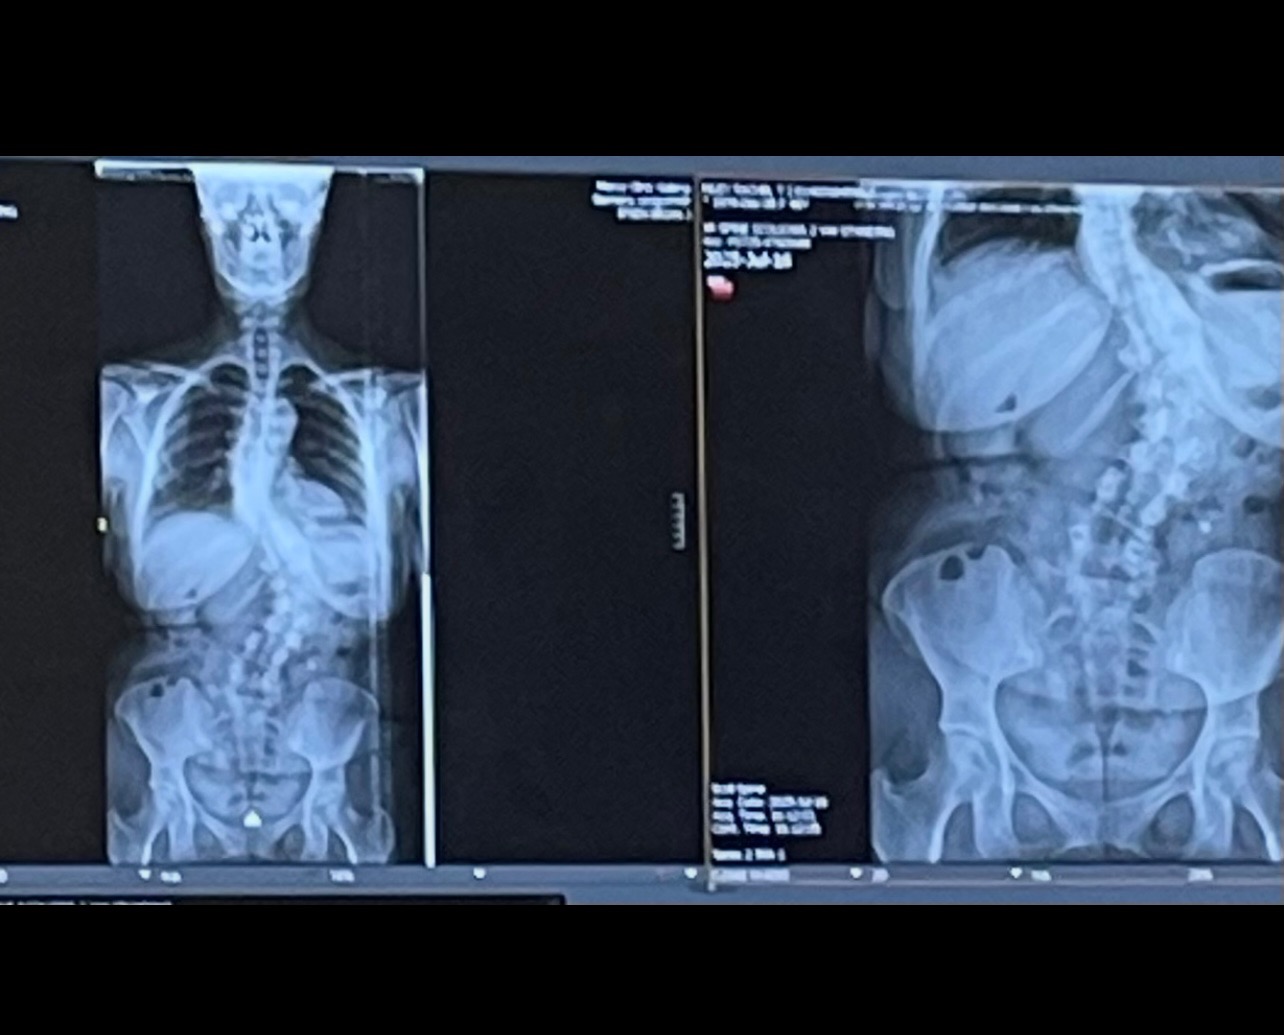

Hello, I’m Rachel and I’m having surgery to correct my severe scoliosis in early October.

Life happened, and I didn’t have the capability to get help. Unfortunately, the pain got to a point where getting help was the only option. I’ve had X-rays and MRIs and quit smoking. I’m doing all the things to make sure this is a success!